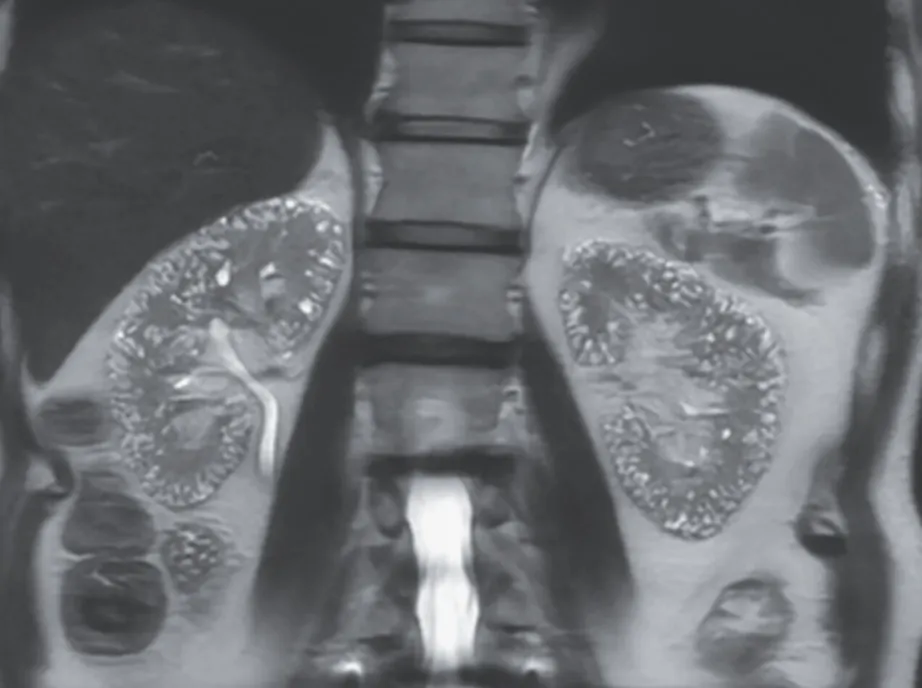

A tomografia computadorizada de abdome revelou um rim direito aumentado, com a presença de um cálculo coraliforme na junção ureteropélvica, atrofia cortical e dilatação do cálice, uma aparência referida como o "sinal da pata de urso."

Foi iniciado tratamento com antibióticos intravenosos e realizada uma nefrostomia percutânea. A cultura da drenagem identificou o crescimento de Proteus mirabilis. Após avaliação com cintilografia, foi identificada a ausência de função renal no rim direito, levando à realização de uma nefrectomia.

Foi feito o diagnóstico de pielonefrite xantogranulomatosa.

A pielonefrite xantogranulomatosa, uma forma de pielonefrite crônica, está tipicamente associada à obstrução por cálculos e infecções recorrentes do trato urinário. As complicações podem incluir abscessos e fístulas. A perda da função renal é comum, e a nefrectomia é o tratamento definitivo. O paciente recebeu alta 5 dias após a cirurgia e apresentava-se bem, com função renal estável, após 1 mês de acompanhamento.